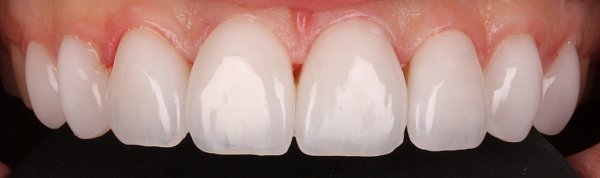

Пациентка обратилась по эстетическим показаниям, изначально у нее выявлено: недостаточная ширина улыбки, снижение высоты нижней трети лица, отсутствие плотного смыкания зубов в боковом отделе, сужение зубных рядов. Так же пациентка была очень недовольна формой и цветом передней группы зубов. Был поставлен диагноз — Мезиальная окклюзия. Сужение зубных рядов. Нарушение эстетики.

Основные пожелания пациентки — иметь ровный зубной ряд с правильным смыканием и положением зубов, но

Что было сделано:

-

Выровняли дугу улыбки с помощью

брекет-системы и техники многопетлевых дуг. - Провели коррекцию соотношения челюстей, добились нормализации формы и размеров зубных рядов.

- В области передней группы зубов были оставлены промежутки, для возможности увеличения размеров зубов

- Ортопедом фиксированы цельнокерамические виниры. Цвет и форма подбирались совместно с пациентом.

В итоге зубы стали не просто ровными, а идеальными: по форме и размерам. И цвет- главное пожелание пациентки — ослепительно белый! Результат на лицо!

Комплексный план лечения реализовала команда врачей: ортодонт Десяткина А.В., ортопед Десяткин И.М.